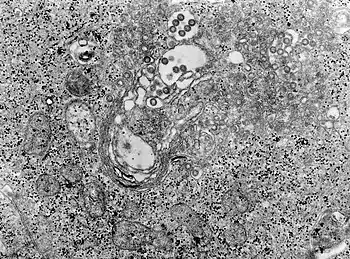

TEM micrograph of tissue infected with Rift Valley fever virus -